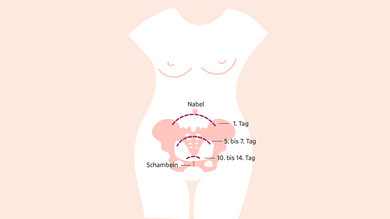

Rückbildung der Gebärmutter

Während der Schwangerschaft und nach der Geburt leistet die Gebärmutter Unglaubliches: Ist das Baby frisch auf der Welt, wiegt sie etwa ein Kilogramm. Zum Ende des Wochenbetts ist sie mit etwa 50 Gramm wieder so schwer wie vor der Schwangerschaft. Sie nimmt also um das Zwanzigfache zu und wieder ab.

Für Hebamme Susanne Huhndorf aus Hannover ist vor allem die Größe entscheidend. „Kurz vor der Geburt befindet sich die Gebärmutter ein bis zwei Querfinger unter dem Rippenbogen“, erklärt sie, „unmittelbar danach auf Höhe des Nabels.“ Um in ihre ursprüngliche Position zurückzukehren, zieht die Gebärmutter sich immer wieder zusammen. Dabei kann es zu Nachwehen kommen. Nach etwa 14 Tagen ist das Organ zurück an seinem Platz.